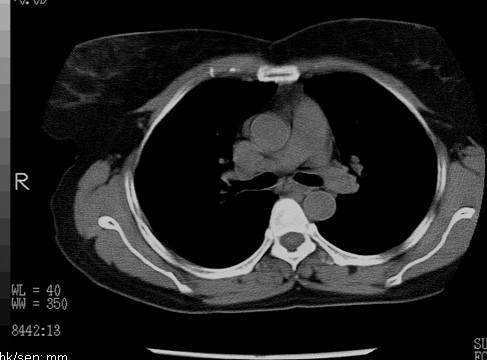

以下是引用随光逐影在2010-3-1 8:36:00的发言:[br]右上纵隔囊性占位性病变,考虑支气管囊肿,不排除神经源性肿瘤。